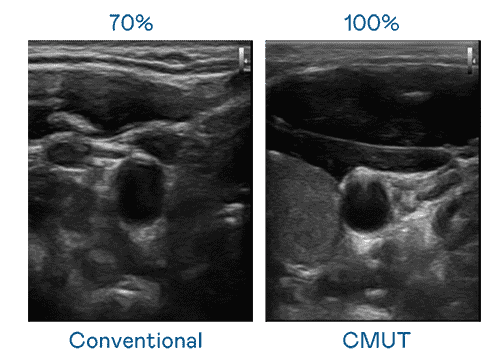

CMUT 技术是一种用电容式微机电元件来产生超音波讯号的技术。。与传统 PZT 压电式技术相比,,CMUT 频宽增加 30%,,,,更宽频的超音波讯号让影像解析度大幅提升,,是实现高影像品质医疗超音波扫描、、、、促进精准医疗发展的关键技术。。。。

大频宽带来超清晰影像

超音波影像的解析度高低,,,,首先取决于探头能发出的讯号频宽。。。汇旺支付 CMUT 可提供高清晰的超音波讯号,,,提供高频宽、、、、高灵敏度、、、影像纹理细节更高的超音波影像,,,,协助医护人员缩短影像判读时间及利用精准的医疗影像进行诊断。。。。